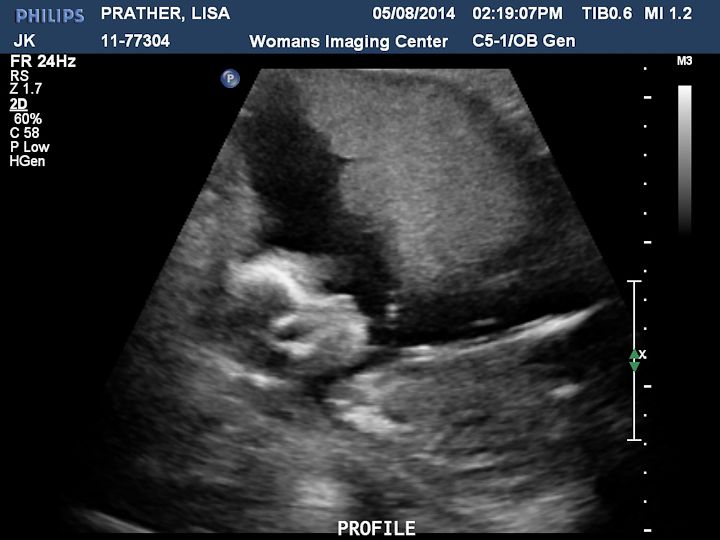

Here are some pictures we got. There is a description on each picture of what you are looking at.

The baby was moving a lot and kept turning it's head right towards us.